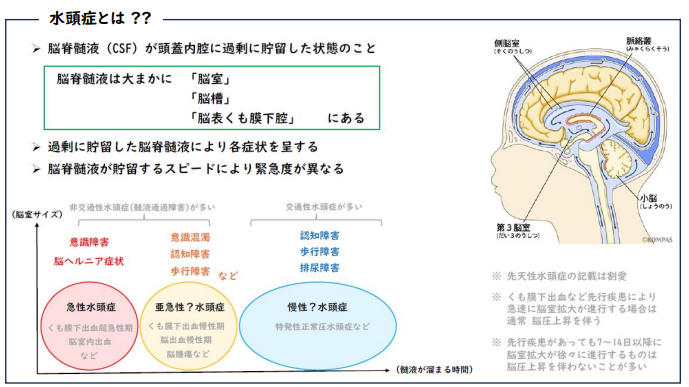

脳や脊髄は髄膜(くも膜)という膜でできた袋で、この中を満たすお水の中にぷかぷか浮いています。このお水のことを脳脊髄液と言います。脳脊髄液は脳脊髄への栄養因子やホルモンの運搬、老廃物の排泄、外力の緩衝など様々な機能があると言われています。通常、脳脊髄液は適切な量になるように産生と吸収がうまく調整されていますが、様々な原因で脳脊髄液が増えてしまいます。

脳脊髄液が増えて脳室(脳の中にある髄液がたまっているところ)が拡大した病態を水頭症と言います。

正常圧水頭症とは髄液圧が正常のものをいい、脳の圧が上がらないため命に係わることはありませんが、生活に影響する症状を起こしてきます。正常圧水頭症は、「先天性」「二次性(くも膜下出血後、髄膜炎後、外傷後など)」「特発性」「家族性」に分類されています。